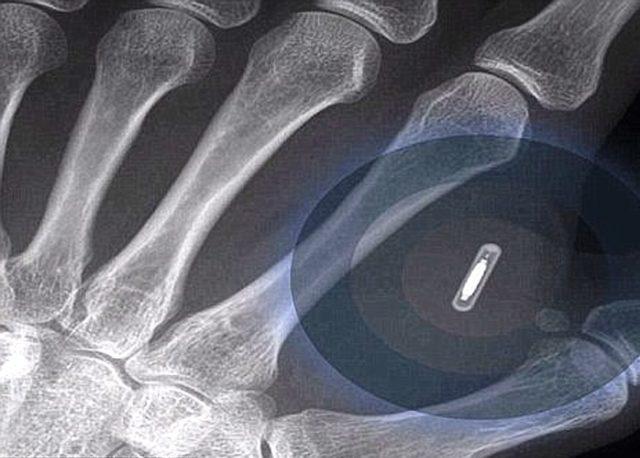

Implantovanie čipu do ľudského tela možno prirovnať k tetovaniu. Pod kožu sa dostáva pomocou väčšej ihly a podľa väčšiny osôb, ktoré podstúpili biohacking, ako sa čipovanie nazýva, to vraj nie je bolestivá procedúra, pripomína len štipnutie.

Plošne implantovaný čip má zatiaľ len určité preddefinované funkcie, ako je napríklad otváranie dverí alebo cestovné na vlak. V podstate je to taká istá technológia, ako funguje pri zamestnaneckých kartách na vstup do budov. Podľa oficiálnych vyjadrení vraj súčasné čipy neumožňujú sledovanie osoby, v ktorej tele sa nachádzajú. Vedci sa pritom odvolávajú na fakt, že ak chce niekto niekoho sledovať, bez problémov to dokáže pomocou smartfónu alebo platobnej karty, ktorou platíme na určitých miestach.